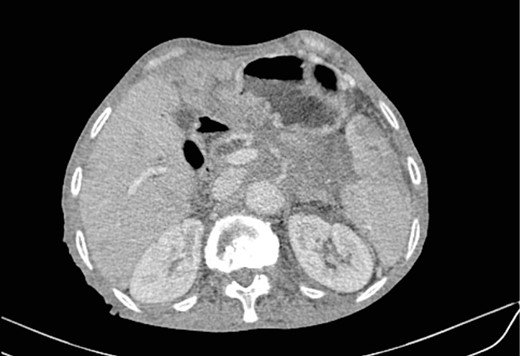

Mr. B. is a 59-year-old patient with no notable pathological history, presenting with melenas associated with marked weight loss. A fibroscopy revealed a thickened and ulcerated gastric mucosa. Abdominal and pelvic CT scans revealed a tissue process in the body and tail of the pancreas invading the splenic hilum, adjacent vessels ans gastric wall, measuring 11 cm long (Fig. 5). A caudal spleno-pancreatectomy enlarged to the colon, omentum and stomach was performed. Macroscopically, the tumor had a grayish–white appearance, poorly limited and indurated on palpation. Histologically, it was a well-differentiated, keratinizing squamous cell carcinoma of the tail of the pancreas (Figs 6 and 7), infiltrating the splenic hilum, gastric wall and colon.

HE section: Neoplastic cells have densely chromatic enlarged nuclei with prominent nucleoli. They are enlarged with abundant eosinophilic cytoplasm and focal keratinization. Intercellular bridges are slightly visible (x200).